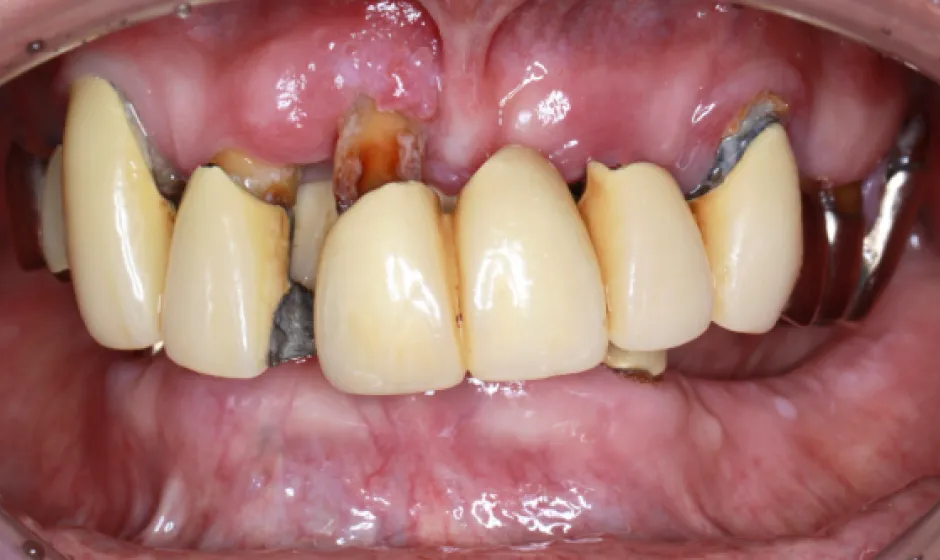

03歯がボロボロの方への

全顎治療むし歯や歯周病が広がり、「どこから治せばいいのか分からない」状態は、痛みだけでなく食事や会話、見た目のストレスにもつながります。医療法人大杉歯科医院では、まず精密に検査し、残せる歯・治療が必要な歯を見極めたうえで、治療の優先順位を整理します。仮歯で噛み合わせを整えながら、補綴やインプラントなどの選択肢を組み合わせ、機能と審美の両立を目指します。

いきなり理想を押しつけるのではなく、現実的に続けられる計画で、お口全体を立て直す治療をご提案します。症例1

症例2

- 治療名

- 重度虫歯からの全顎インプラント治療

- 患者様

- 40代男性

- 執刀医

- Dr. 大杉

- 治療期間

- 1年

- 治療費

- 上顎:3,630,000円(税込)

下顎:3,630,000円(税込) - リスク

- 術後、硬い物を食べないでください。

インプラントが骨に結合するまで2ヶ月かかります。

この期間中に強い負荷をかけると、結合しないことがあります。